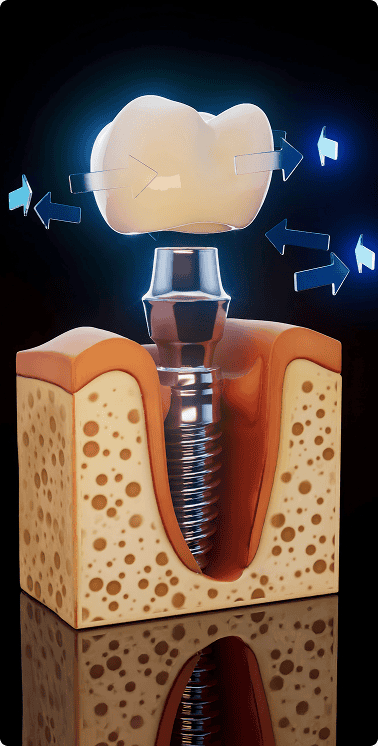

Impianti dentali

Gli impianti dentali vengono utilizzati per sostituire i denti mancanti e fungono da base solida e permanente per corone o ponti. Hanno un aspetto e una sensazione simili ai denti naturali e aiutano a ripristinare l’equilibrio del sorriso, la funzione masticatoria e la struttura del viso.